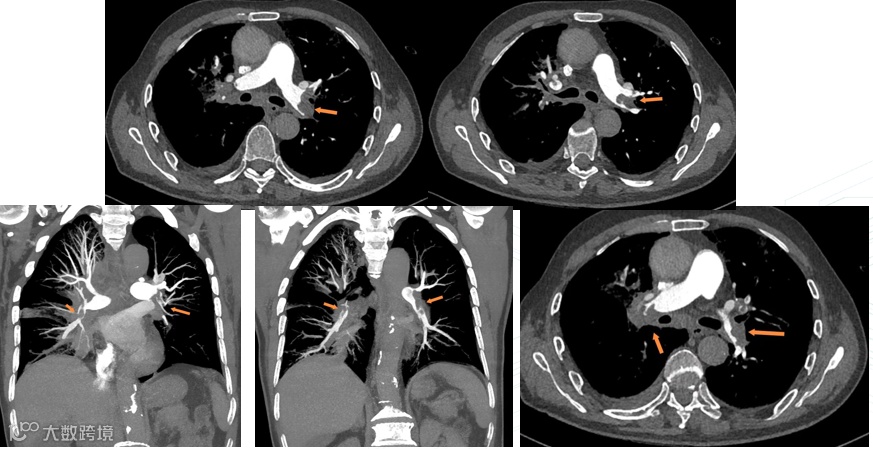

术前检查

手术过程